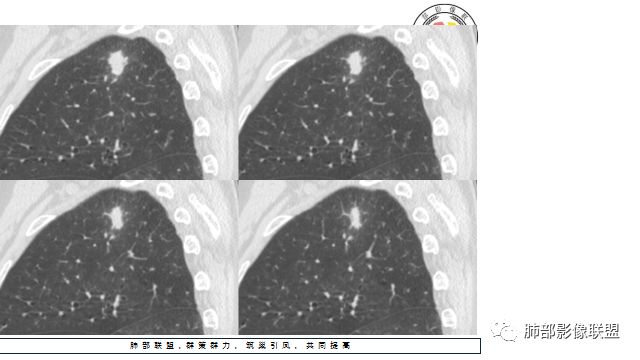

晨读:患者中老年男性,咳嗽 咳痰伴痰中带血2天,发现右上肺结节入院。

胸CT:右上肺结节,病灶位于胸膜下,边缘可见平直 u型征 软毛刺 晕,增强可见延迟强化,病灶中心低密度区。

2.右肺尖类圆形结节影,边界清楚,未见明显分叶或深切迹,部分分边缘较平直,可见细长毛刺棘状突起,相邻胸膜增厚,未见胸膜凹陷。后段胸膜下见条索影及微小结节影。

相关血管未见脐凹,有限图像层面未能显示相关支气管情况。